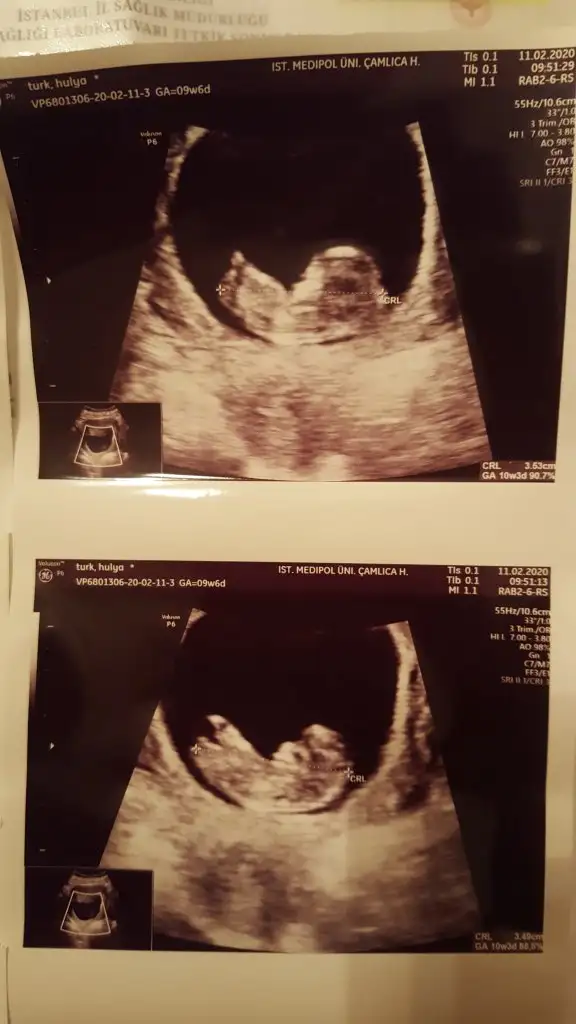

dr soylemeden siz gorun genital nub teorisi ( bebegin cinsiyeti)

Merhabalar Tahmin yorumlarınızı heyecanla takip ediyorum. Bende sabırla 12. haftamızın dolmasını bekledim. Bir yorumda benim için yaparmısınız Buğün 12+1 olduk.

Tam net değil usg dr çıktısı yokmu bu usglerde emin olamadım sanki diyerek kız gibi gibi tekrar usg bekliyorum

Var tabiki ama ne olmadığı için ekran fotoğrafı yolladım